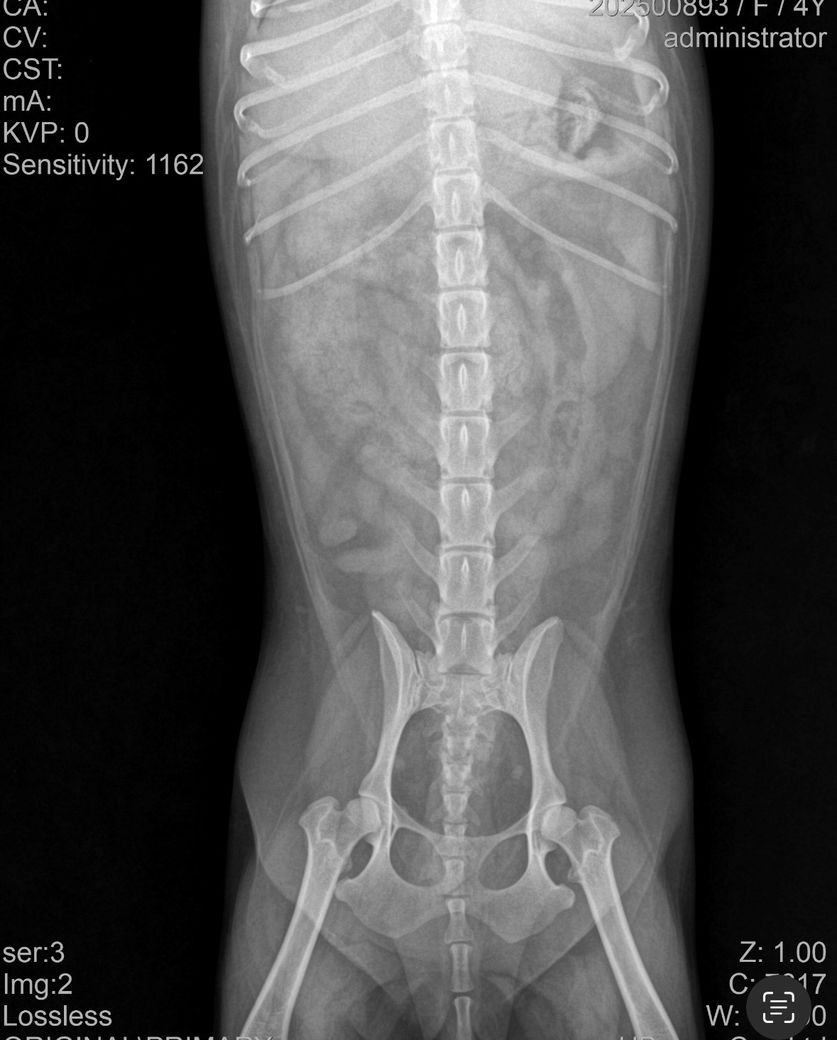

• 엑스레이, 초음파 검사 진행

• 검사 결과: 이물 가능성 있음, 확실하지 않음

4. 첨부 엑스레이에서 이물 여부 확인 가능 여부

엑스레이에서는 명확한 이물이 보이지 않을 수 있습니다. 플라스틱, 실, 천조각처럼 방사선 불투과성이 낮은 이물은 거의 보이지 않기 때문에 초음파로 확인하거나, 장 내 액체 정체나 장 운동 저하로 간접적으로 의심하는 경우가 많습니다. 물을 마셔도 바로 토하는 패턴은 위에서 내용물이 내려가지 못하거나, 위 자체가 심하게 자극된 상황에서 흔히 나타나며 이물 가능성과 위염 두 가지 모두에서 보일 수 있습니다.

첨부한 사진은 복배상의 사진밖에 없고 외측상이 없어 판독할 수 없습니다. 방사선 사진은 원래 앞사진, 옆사진 이렇게 최소 2장이 필요합니다.